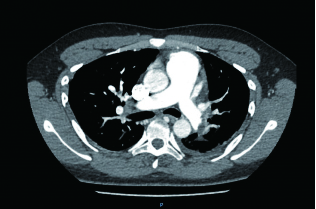

2 积极寻找补救性溶栓的治疗时机并非遥不可及例3 36岁,女性。主诉“活动后气短5 d、加重伴咯血1 d”。既往因月经不调,应用激素替代治疗20 d;否认手术、外伤及制动史。入院查体:神志清楚,体温36.8℃,血压110/75 mmHg,脉率118次/min,呼吸23次/min,脉氧饱和度90%(安静,空气氧),轻度乏氧征。双肺呼吸音清。心率118次/min,未闻及干、湿性啰音,心律齐,P2 > A2,心界无扩大,无杂音,腹软,无压痛,肠鸣音正常,双下肢无浮肿。神经系统查体未见异常。血气分析(空气氧)提示pH 7.415,PaCO2 38.3 mmHg,PaO2 89.90 mmHg,SaO2 89.90%;D-Dimer 1 684 ng/mL;FDP 8.670 μg/mL,FBG 3.510 g/L;PLT 151.0 G/L;cTnI 0.00 ng/mL,BNP 58.00 ng/mL;ALT 27 U/L,AST 17 U/L,CREA 53.7 μmol/L,血Na+、K+、Cl-大致正常;UCG提示:右室壁运动减低,左室壁运动不协调,各室壁厚度正常,三尖瓣环位移14 mm,右室面积变化率19%,各瓣膜形态及运动未见异常,收缩期三尖瓣房侧见少量反流信号,T1法估测SPAP:24 mmHg;双下肢静脉超声提示:右下肢深静脉血栓形成。心电图(图 8所示)提示窦性心动过速;CTPA提示双肺主干明确充盈缺损(图 9所示)。入院诊断:急性PE(中低危)。给予低分子肝素抗凝治疗。入院24 h内,大便时出现胸闷、心悸主诉,SpO2由93%(不吸氧)降至88%(储氧面罩吸氧,Flow 10 L/min);D-Dimer由入院时1 026 ng/mL升至4 100 ng/mL,血压110/70 mmHg。因血氧有恶化趋势遂决定给予静脉溶栓治疗(r-tPA 50 mg,2 h内泵入),溶栓治疗结束后2 h复查凝血提示D-Dimer 45 000 ng/mL。溶栓2 h患者症状明显好转;心电图提示窦性心动过速,SⅠQⅢTⅢ征象较前改善,胸前导联出现冠状T波(图 10所示)。溶栓后24 h复查CTPA右肺主干血栓明显消失,右心室较前明显缩小(图 11所示)。

| 图 9 入院时CTPA提示右肺动脉主干充盈缺损、左肺亚段水平充盈缺损、右心室增长 |

| 图 11 溶栓后CTPA提示原有血栓完全溶解、右心室较前明显缩小 |